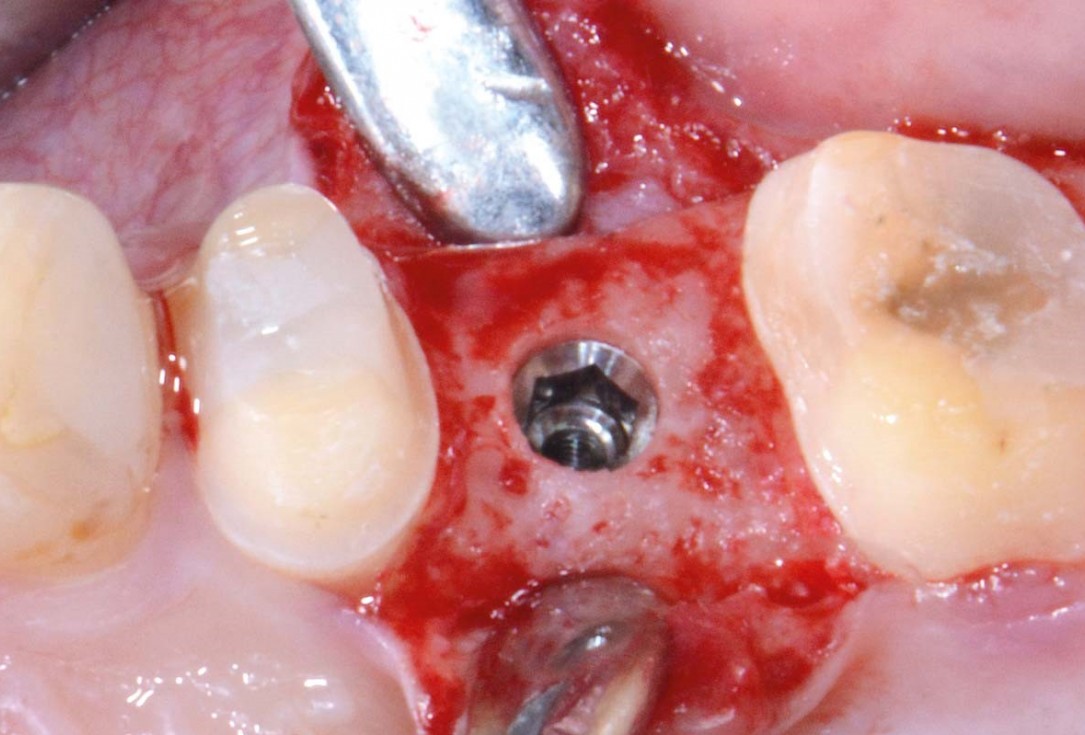

12/16 - Implant placement in fully regenerated boneFull bone regeneration in extraction socket augmented with maxgraft® and Jason® membrane – Dr. C. Landsberg